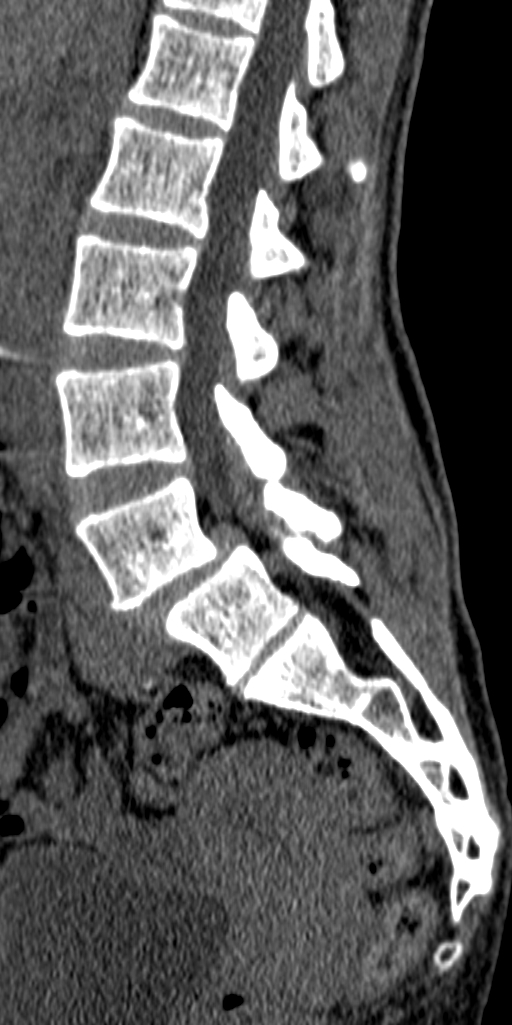

КТ ПОП. Девушка 28 лет.

Вот такие изменения.

Антелистез визуализируется очень хорошо.

Спондилолизный спондилолистез обычный вижу тока и люмбосакральный позвонок IV по Castellvi  или асимметричный переходный с односторонней конкресценцией, если по русски. Если не так по-русски, коллеги поправят.

Истинный антелистез L4 1-й ст, грыжа L4-5, асимметричная сакрализация L5. Вероятна компрессия L5 корешка. По Castellvi хорошая классификация, но трудно принимается некоторыми клиницистами).

Спондилолиз, антеспондилолистез 2 ст. L5.

Раз уж занялись некропостингом:

2Любовь С. На глаз согласен с 1-й степенью спондилолистеза. Но если считать переходный позвонок как L5 - получается компрессия нерва L4 в фораминальном окне.